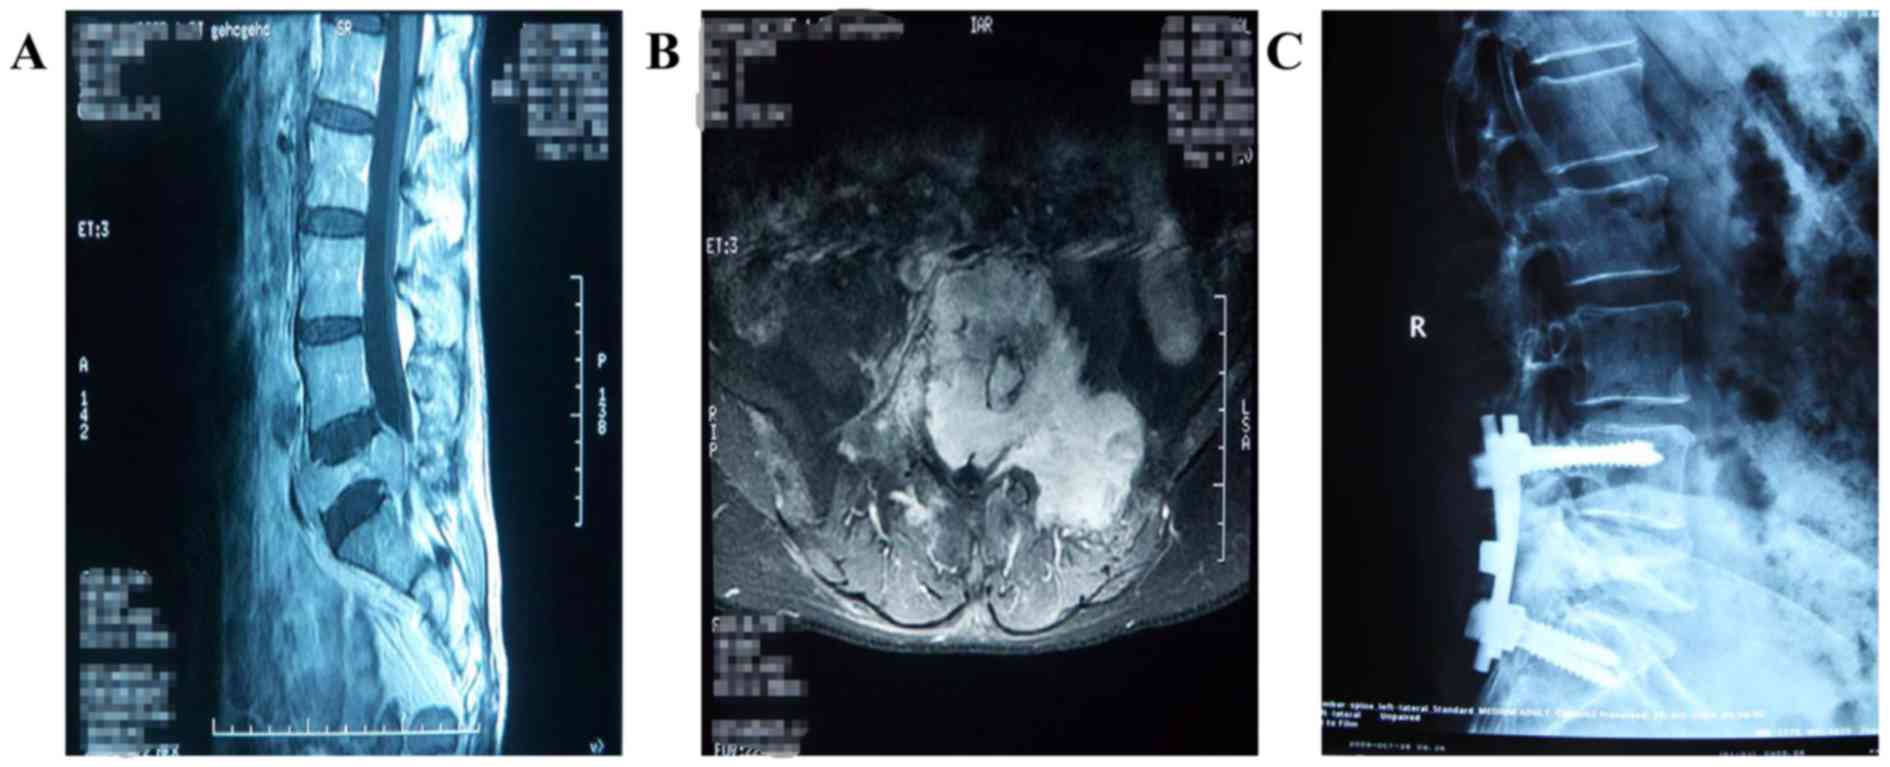

Figure 1.

Magnetic resonance imaging and X-ray plain film were used to examine one patient from group A. (A) Magnetic resonance imaging examination revealed that the lesion was located in the spine, the vertebral body of L5 was severely destroyed, and the lumbosacral dural sac was evidently compressed. Image obtained prior to surgery. (B) In this coronary scanning of magnetic resonance imaging examination, lesions were observed to be protruded towards the left and back. Image obtained prior to surgery (C) A postoperative X-ray plain film scan indicated that the fixation devices were implanted successfully. Image obtained following surgery.